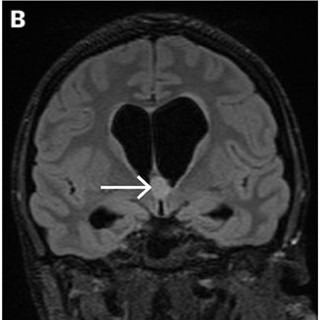

Rolf Hanoa Nevrokirurgisk avdeling Rikshospitalet og Ullevål sykehus 1951 - 2021 Norsk helsepolitikk for nevrokirurgiske pasienter. 416 s., tab., ill. Bergen: Fagbokforlaget, 2023. Pris NOK 549 ISBN 978-82-450-4320-4 Boken tar med leseren på en interessant reise, fra pionertiden til moderne tid, i nevrokirurgi ved Rikshospitalet og Ullevål sykehus. Vi får innblikk i en enorm fagutvikling, historiske milepæler, noen nedturer samt en lang rekke omorganiseringsprosesser. Boken er mer enn et festskrift til de to viktige norske sykehusavdelingene, men berører også omstridte behandlingsmetoder...